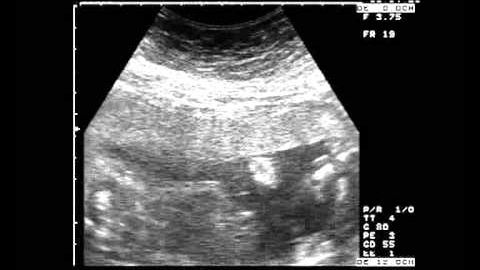

În acea zi ei s-au dus împreună la ecografie. „Veți avea un băiețel, dar cu malformații… Mânuțele lui nu se dezvoltă și toate organele interne sunt mărite…” Apoi doctorița a încercat îndelung să-i convingă pe părinții îndurerați: „Înțelegeți că aceasta este o cruce, pe care va trebui să o duceți toată viața?! Un copil invalid!” — cuvintele ei le străpungeau inimile ca un cuțit. — „Veți fi arătați cu degetul! Veți munci doar pentru medicamente și vă veți ruga ca el să moară mai repede!”

Mai târziu ecografia a confirmat că Nadejda era complet sănătoasă. Iar Olesiei i s-a descoperit un fibrom uterin uriaș. Aparent, anume pe acesta medicii l-au văzut atunci pe ecran. Ea a fost repede operată. Din păcate, a fost necesară îndepărtarea tuturor organelor feminine. Olesia mângâia părul fiicei sale adormite și se gândea îngrozită la ce putea să se întâmple, dacă se lăsa atunci convinsă de doctoriță…